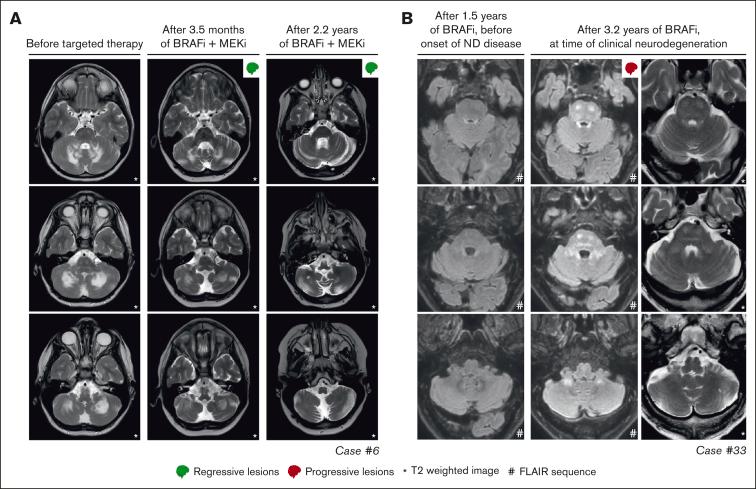

Histiocytic disorders are rare hematologic neoplasms characterized by a notable dependence on mitogen-activated protein kinase signaling. Targeted therapy is an emerging treatment option, yet the number of reported patients remains limited. Here, we describe 40 patients with histiocytic neoplasms who were treated with targeted therapy in 7 tertiary referral hospitals from the Netherlands and Belgium. The cohort comprised of 6 (15%) children and 34 (85%) adults with diverse histiocytoses, including Langerhans cell histiocytosis (LCH; n = 12), Erdheim-Chester disease (n = 14), central nervous system xanthogranuloma (n = 2), Rosai-Dorfman disease (n = 3), histiocytic sarcoma (n = 2), ALK-positive histiocytosis (n = 1), and mixed/unclassifiable histiocytosis (n = 6). Five patients were included in a clinical trial; 35 (88%) received BRAF/MEK inhibitors outside of trials. Among these 35 patients with available follow-up data, median time on targeted treatment was 1.9 years (range, 0.04-5.8 years). Complete or partial responses were observed in 25 of 27 (93%) patients treated for multisystemic and/or solid lesions and 2 of 8 (25%) patients treated for neurodegenerative LCH. Responses were generally durable, although 10 patients lost response after dose reduction or therapy interruption. Responses were recaptured in 9 of 10 cases. Two patients developed new or progressive neurodegenerative lesions: 1 during and 1 after vemurafenib therapy. At last follow-up, 8 adults had stopped targeted therapy because of toxicity. This study corroborates the favorable outcomes of BRAF/MEK inhibition in patients with histiocytosis described previously. However, it also highlights limitations and calls for prospective studies.

组织细胞疾病是罕见的血液系统肿瘤,其显著依赖丝裂原活化蛋白激酶信号传导。靶向治疗是一种新兴的治疗选择,但报告的患者数量仍然有限。在此,我们描述了40例在荷兰和比利时的7家三级转诊医院接受靶向治疗的组织细胞肿瘤患者。该队列包括6名(15%)儿童和34名(85%)成人,患有多种组织细胞增多症,包括朗格汉斯细胞组织细胞增多症(LCH;n = 12)、 Erdheim-Chester病(n = 14)、中枢神经系统黄色瘤(n = 2)、Rosai-Dorfman病(n = 3)、组织细胞肉瘤(n = 2)、ALK阳性组织细胞增多症(n = 1)以及混合/无法分类的组织细胞增多症(n = 6)。5名患者纳入了一项临床试验;35名(88%)在试验之外接受了BRAF/MEK抑制剂治疗。在这35例有可用随访数据的患者中,靶向治疗的中位时间为1.9年(范围为0.04 - 5.8年)。在27例接受多系统和/或实体病变治疗的患者中有25例(93%)以及8例接受神经退行性LCH治疗的患者中有2例(25%)观察到完全或部分缓解。缓解通常是持久的,尽管10例患者在剂量减少或治疗中断后失去缓解。10例中有9例重新获得缓解。2例患者出现新的或进展性神经退行性病变:1例在维莫非尼治疗期间,1例在治疗后。在最后一次随访时,8名成人因毒性停止了靶向治疗。本研究证实了先前描述的BRAF/MEK抑制对组织细胞增多症患者的良好疗效。然而,它也突出了局限性并呼吁进行前瞻性研究。